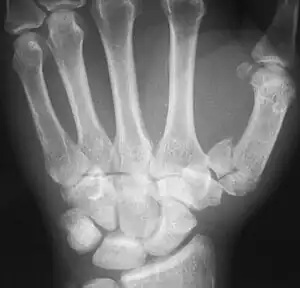

| Rolando fracture - a comminuted intra-articular fracture of the first metacarpal bone. | |

The cause is generally a force along the long axis of the thumb, such as during a fight.[3][4] Diagnosis is by medical imaging; such as X-ray, CT scan, or MRI.[3] It results in at least three bone fragments, which often form a T- or Y-shaped pattern.[3][4] It differs from a Bennett fracture which only results in two bone fragments.[4]